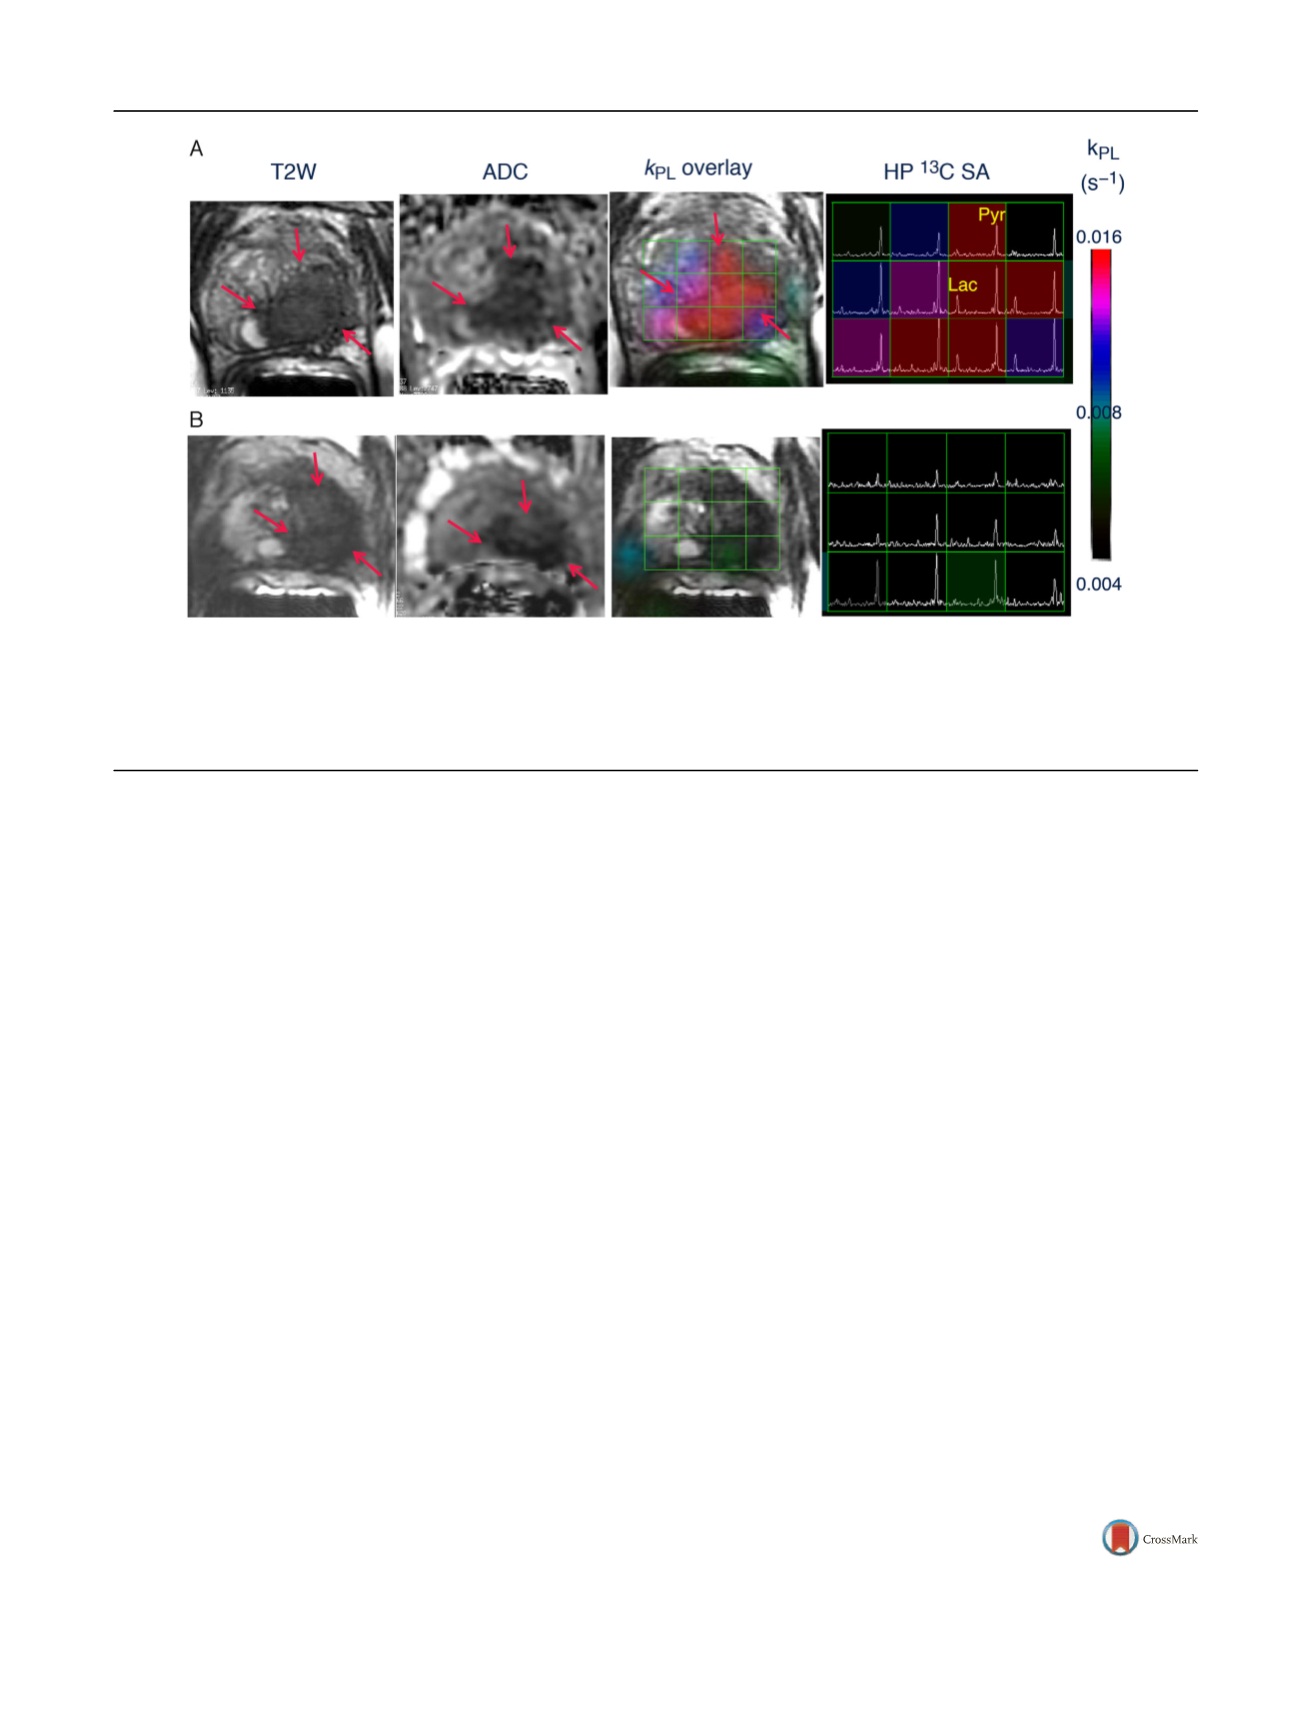

Figure 1A shows the HP

13

C spectral array for the baseline

scan, with markedly elevated lactate peaks within tumor-

containing voxels. A color scale map of dynamic pyruvate-

to-lactate metabolic flux (

k

PL

) values likewise shows

markedly elevated flux levels in the tumor compared to

adjacent normal tissue in the baseline HP [

C]-pyruvate

MRI.

At 6 wk after initiation of ADT, repeat imaging

demonstrated nearly complete abrogation of elevated HP

lactate peaks on HP

C MRI

( Fig. 1B) and associated near

complete diminution of intratumoral

values on dynamic

imaging (

max 0.025 s

1

at baseline and 0.007 s

on

follow-up). Notably, there was negligible change in size of

tumor on T2-weighted MRI and only a modest change on

ADC imaging, supporting the ability of HP

C MRI to detect

early metabolic responses before such a response can be

ascertained using standard radiographic criteria. Concor-

dant with these findings, the patient subsequently achieved

a marked clinical response, with an undetectable serum PSA

nadir at 6 mo after ADT initiation.

Fig. 1

–

Representative axial T2-weighted (T2W) anatomic image and corresponding water apparent diffusion coefficient (ADC) image and T2W image

with an overlaid pyruvate-to-lactate metabolic flux (

) image and corresponding hyperpolarized (HP)

C spectral array (SA) for a 52-yr-old prostate

cancer patient with extensive high-grade prostate cancer (A) before therapy and (B) 6 wk after initiation of androgen ablation and chemotherapy.

Before treatment, the region of prostate cancer can be clearly seen (red arrows) as a reduction in signal on the T2W and ADC images, and increased HP

lactate and associated

flux on HP

C MRI. After initiation of androgen deprivation therapy there was a significant reduction in reduction in HP

lactate and

to normal levels, with only a modest treatment effect on prostate volume and ADC.